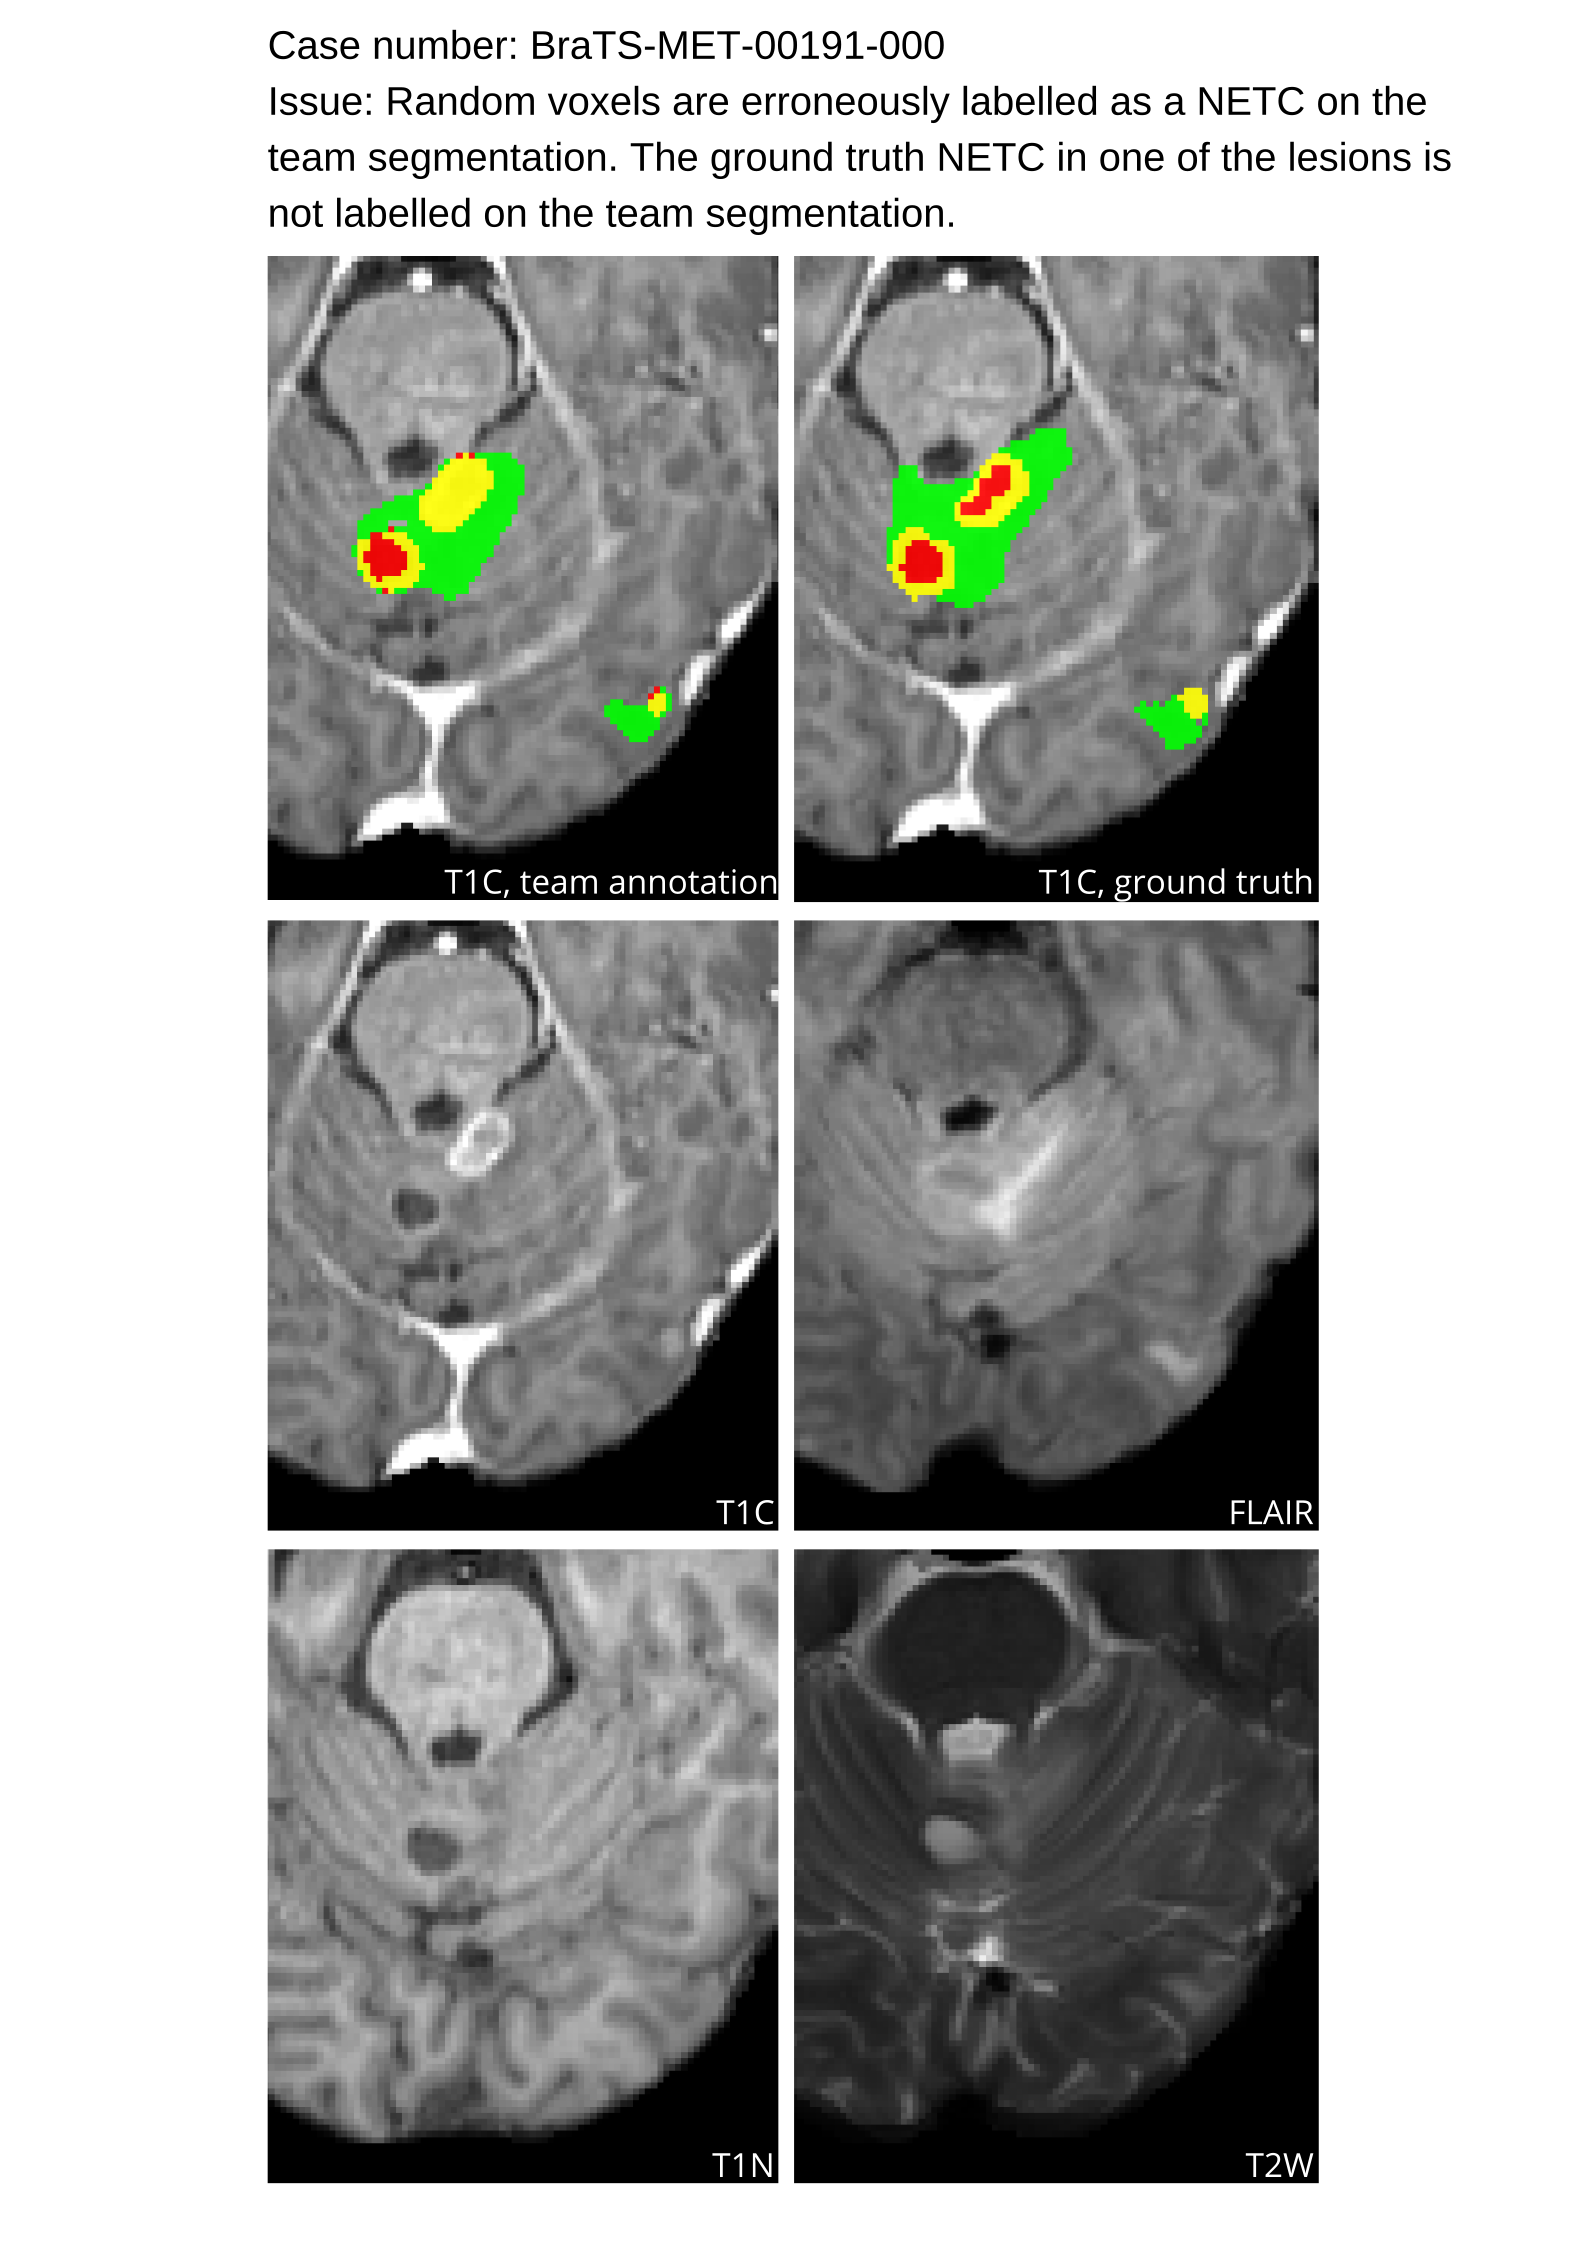

Table 4 provides the relative ranking for each team. Team NVAUTO ranked first in the challenge, with an average rank across subjects of 7.9 and a PatientWise mean of 0.38. Team SY placed second with a PatientWise mean of 0.41 across all patients. The supplementary material depicts the pitfall cases with figures illustrating the false positives or missed lesions.